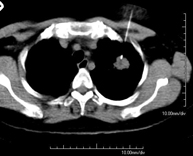

- Chest CT

Diagnostic test that provides high definition anatomical images of the chest (lungs, heart, mediastinum, great vessels, rib cage, etc.) using CT (Computed Tomography) equipment. These images are then examined on a workstation that allows bidimensional reconstructions in different planes of space and also 3D reconstructions (volumetric). Some studies require the use of an iodinated contrast agent to improve image definition.